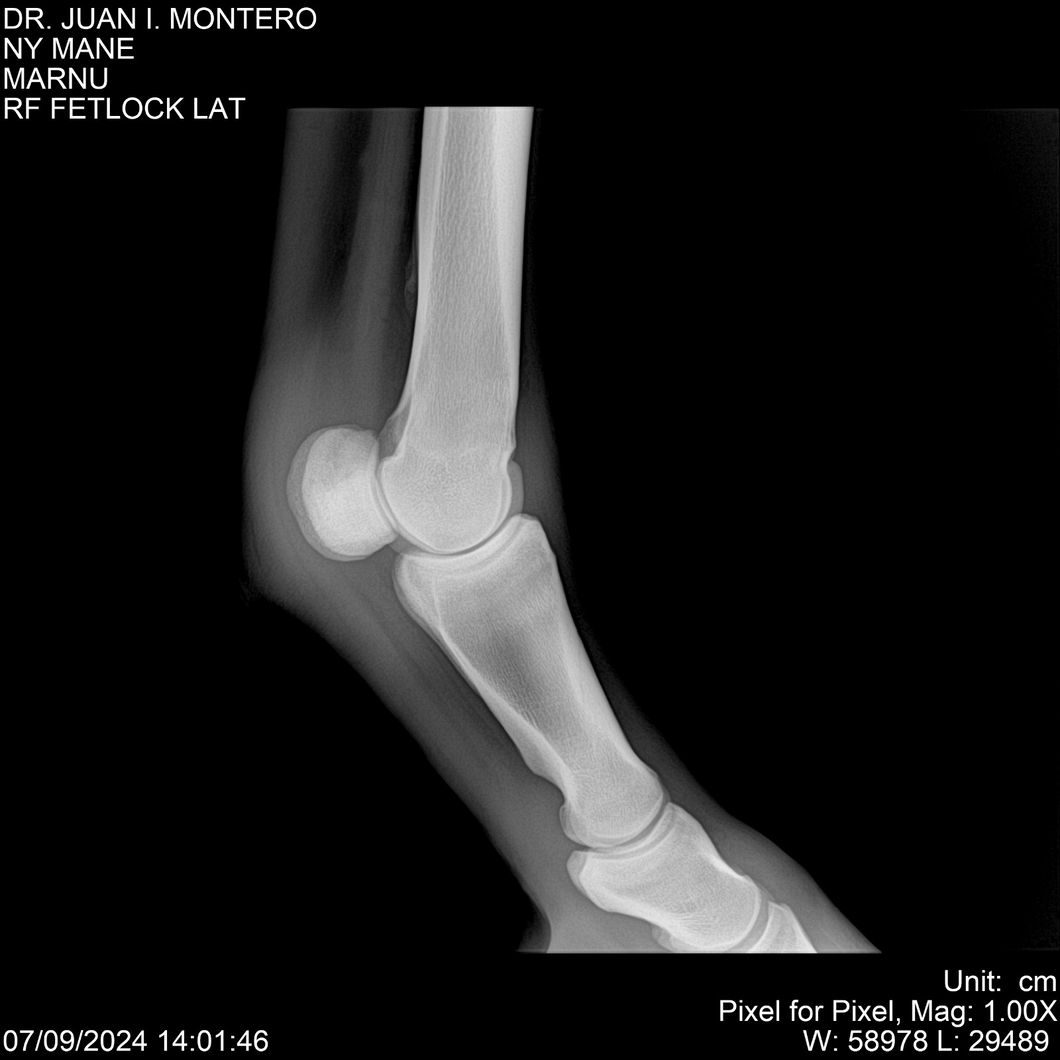

LOTE 20, NY MANE Lote Anterior Volver al remate Lote Siguiente Ficha Contacto Montevideo - Ficha del Lote Identificador: #282520 Categoría: Yeguarizos 76 Visualizaciones ClicData Contacto Empresa: Abelenda N. R., Walter Hugo Nombre*: Teléfono* : E-mail* : Mensaje Enviar Registrese gratis Este contenido Exclusivo está disponible sólo para usuarios registrados Ingresar